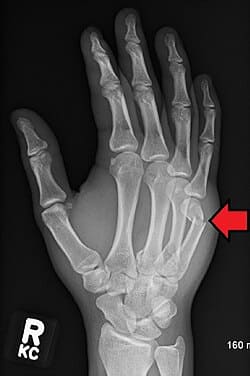

The most common fractures of the upper extremity include finger fractures, hand fractures, and distal radius fractures. Treatment for these fractures varies depending on the location, the type of fracture and the degree of instability.

At The Hand & Plastic Surgery Center of Katy, our hand surgeons are experienced in treating all types of upper extremity fractures including small joint finger fractures, metacarpal fractures, scaphoid and other wrist fractures, as well as distal radius fractures. They will work with you to obtain the proper diagnosis and determine a tailored treatment plan that fits your needs.